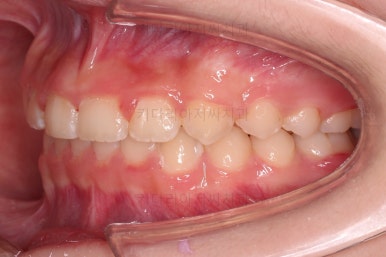

초진 시 입안의 모습입니다.

그리고 전반적으로 아래 치열이 윗니에 비해 뒤로 밀려 있어서, 어금니의 맞물림이 좋지 못하고 듬성듬성해 보이는 상황이었어요.

과개교합, 옥니, 앵글씨 2급 부정교합 모두 좋아지고 있어요.

앞니 각도가 매우 좋아졌고요.(옥니 개선) 위아래 앞니가 덮는 정도도 개선이 되었어요.(과개교합, 딥바이트)

엉성했던 어금니 맞물림도 매우 좋아졌어요.(앵글씨 2급 부정교합 개선)